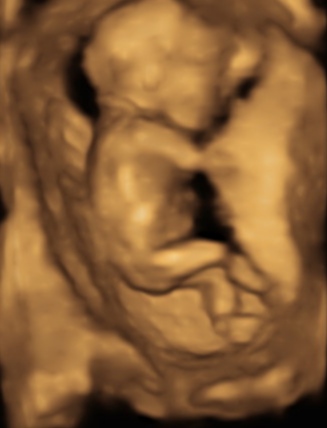

sizce cinsiyetimiz kesin belli mi

Bacak arasını göstermiş ama çokta net değil bende bi çıkıntı gördüm ama sanki kordon gibi ya

Doktorum bugün erkeğe benzetti hem yapısı gereği hemde çıkıntı gördüğünü söyledi

Renkli ultrasonu oğlumunkine çok benziyor ama bacak arasındaki çıkıntıdan ben emin olamadım

14+4 haftalık bu resimde